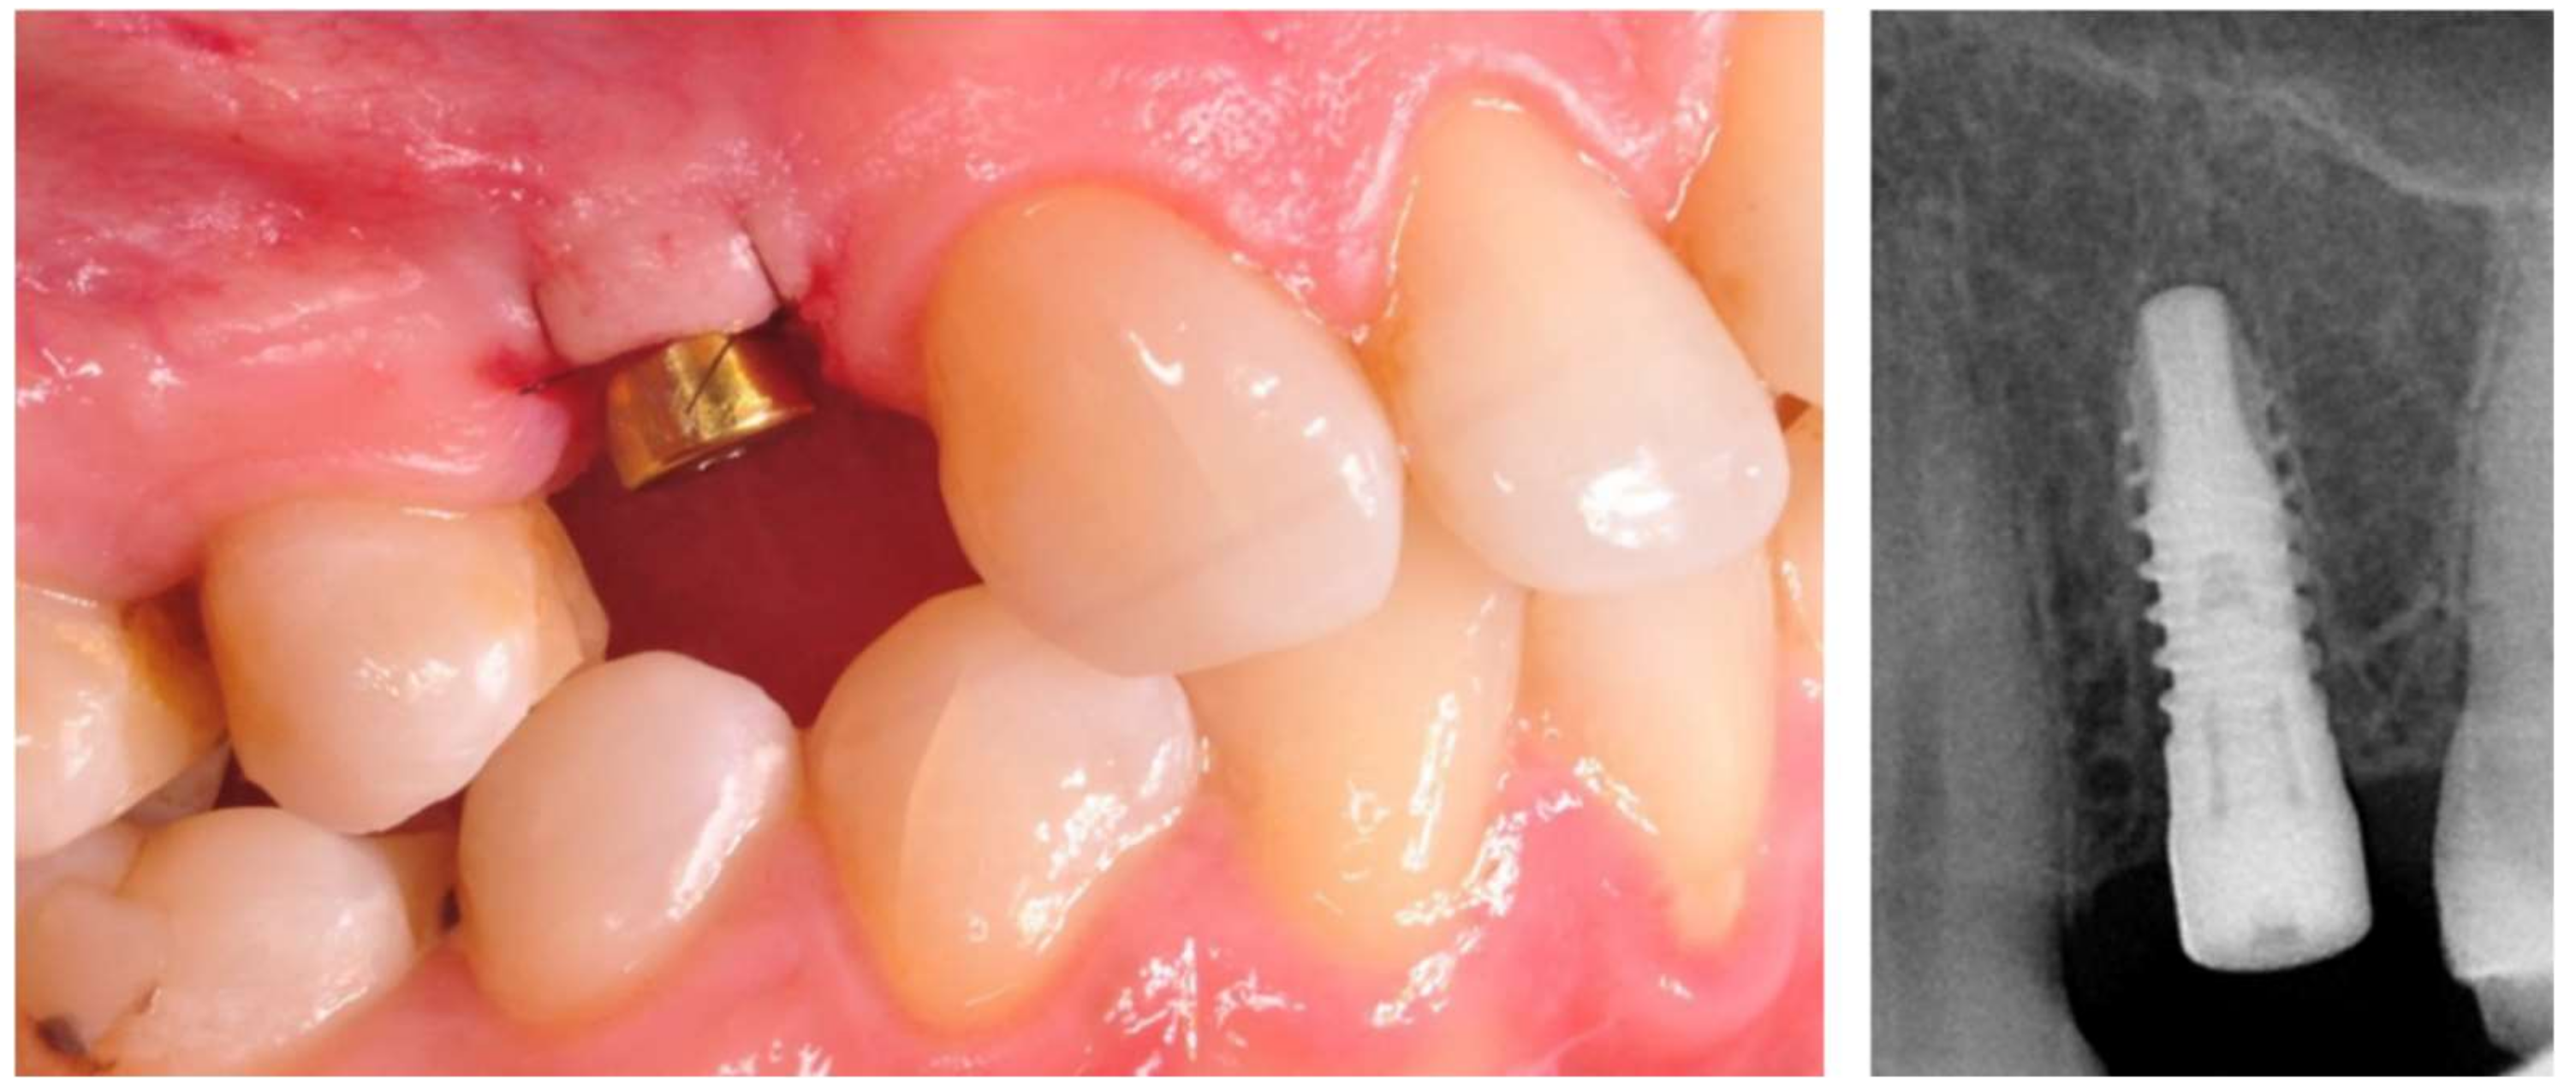

The prosthetic restoration stage started 4 weeks after the implant placement surgery and was prepared in the chairside laboratory by W.G. Patients with no signs of inflammation in the direct vicinity of the implant and with an ISQ (implant’s stability quotient) value of 65 or greater were allowed to participate in the prosthetic protocol. The measurements using the aforementioned device were performed three times in the mesiodistal, buccal and palatal, as well as periapical direction, and the smallest value was considered the cut-off point. Screw-retained implant crowns made of lithium disilicate glass-ceramics, IPS e max CAD LT (Ivoclar Vivadent AG, Schaan, Liechtenstein), were used as the prosthetic restoration materials. After the removal of the healing abutment, the implant bed was cleaned. The scans were taken with an intraoral scanner Sirona Cerec AC Bluecam (DentsplySirona, York, PA, USA) (Figure 2). Subsequently, the crown internal surface was etched and then fixed using Multilink Hybrid Abutment cement (Ivoclar Vivadent AG, Schaan, Liechtenstein) on the previously sandblasted titanium base (TiBase) for Sirona Cerec (DentsplySirona, York, PA, USA). The crown was then screwed onto the implant with a force of 25 Ncm. The occluding relations were controlled using articulating paper (Bausch®, Cologne, Germany) with a thickness of 200, 80, and 8 μm. The hole was filled in with Gradia composite (GC Corporation, Tokyo, Japan) and an RVG image was taken (Figure 3). The patients were instructed on proper hygiene around the dental implant.

Figure 2. Implant with scanbody prepared for intraoral scan.

Figure 3. Implant loaded with the screw-retained crown.